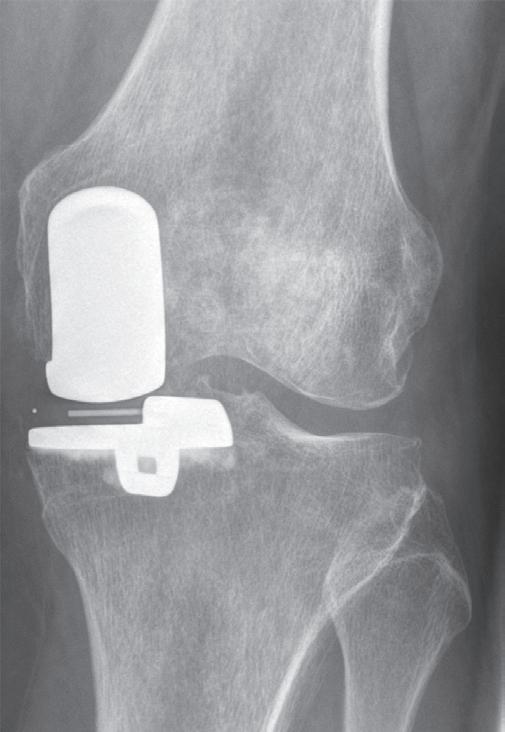

Při poškození pouze mediálního kompartmentu kloubu bez větší osové odchylky je metodou volby hemiartroplastika za použití speciálního implantátu (obr. 19.10, obr. 19.11). Tento výkon pacienta poměrně málo zatěžuje a rehabilitace je jednodušší než u osteotomie nebo totální endoprotézy. Podmínkou je nepoškozený přední zkřížený vaz a dobrý stav patelofemorálního kloubu. U mladších nemocných si obvykle po přibližně 15 až 20 letech vyžádá výměnu za totální endoprotézu.

Obr. 19.11: Hemiartroplastika – předoperační (a, b) a pooperační rentgenový snímek (c, d)